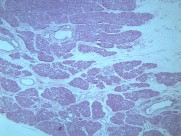

一般认为畸胎瘤多系个体发育初期,部分多能性原始细胞迷离出来,在纵隔内增殖发展成肿瘤。这类肿瘤以良性畸胎瘤多见。常位于前纵隔。畸胎瘤多为实质性,可同时存在大小不等的囊腔,内含外、中或内胚层组织的衍生物如毛发、牙齿、软骨、平滑肌、支气管或肠壁等。部分畸胎瘤可以恶变。由未分化成熟组织构成的畸胎瘤属恶性,呈浸润性生长。畸胎瘤与邻近组织粘连或穿破入邻近脏器如肺、支气管,病人可咳出毛发或皮脂样物。皮样囊肿是一种单房或多房薄壁囊肿,因囊内多衬以鳞状上皮及其附属物而得名。囊内有结节状物、毛发及皮脂类物。